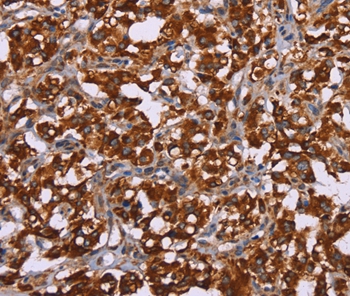

Immunohistochemical analysis of paraffin-embedded Human cervical cancer tissue using #36385 at dilution 1/60.

Immunohistochemical analysis of paraffin-embedded Human thyroid cancer tissue using #36385 at dilution 1/60.